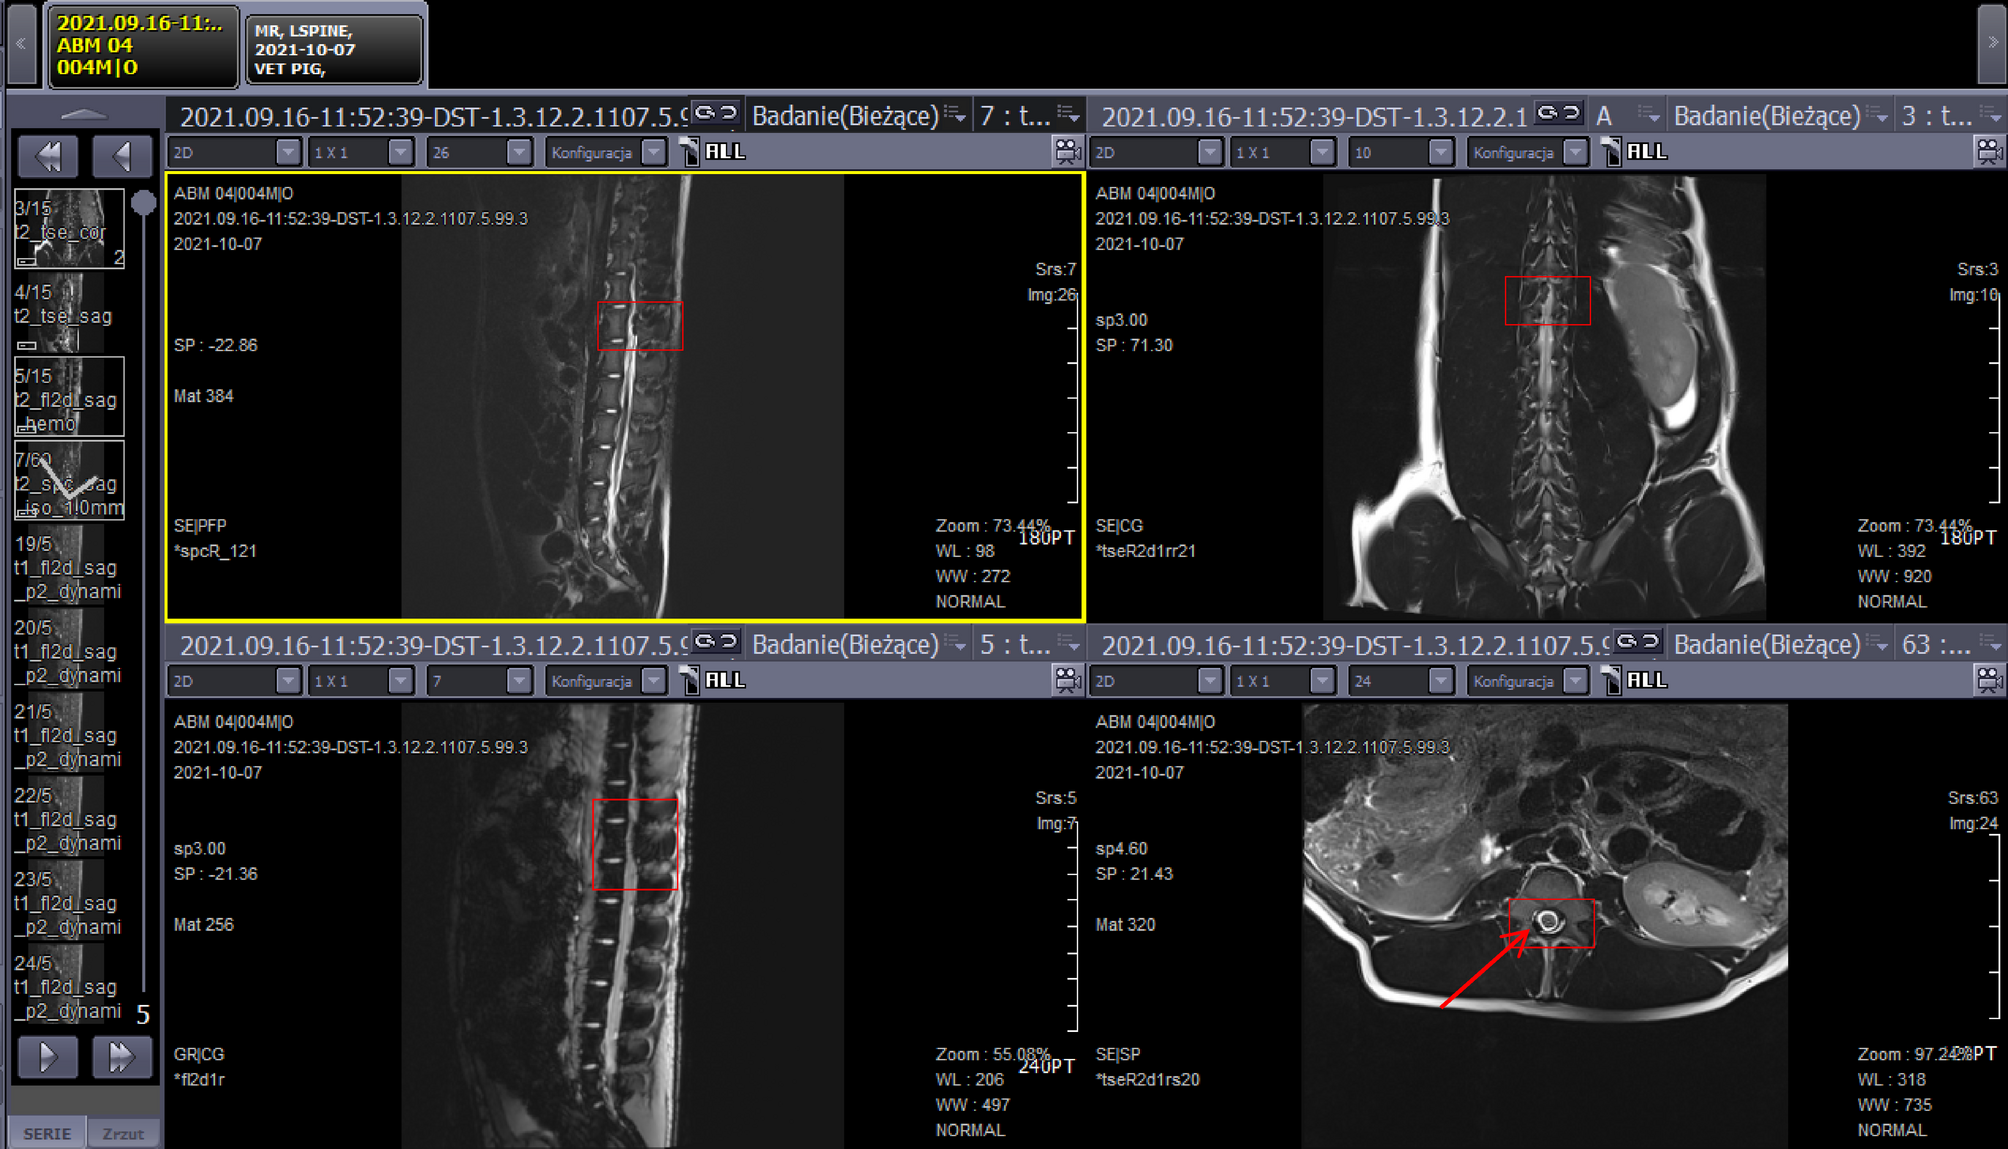

Fig. 9

MRI detection of iron-labelled Wharton’s Jelly–derived mesenchymal stem cells (WJ-MSCs) in the cerebrospinal fluid after intrathecal infusion. MRI images obtained during and after cell administration showing characteristic hypointense areas (marked by red arrows and frames) corresponding to iron-labelledcells. (A) Sagittal planeview showing the localization of the signal approximately 10 cm above the draininsertionsite; (B) coronalplane confirming the spatial distribution of the signal within the spinal canal; (C) sagittalplane with hemo-expansion sequence allowing enhanced visualization of iron-related hypointensity; (D) transverseplane demonstrating cross-sectional localization of the signal within the cerebrospinal fluid compartment. The hypointenseareas correspond to the presence of superparamagnetic iron-labeled MSCs, confirming their localization within the subarachnoid space and the absence of pathological changes in surrounding tissues.